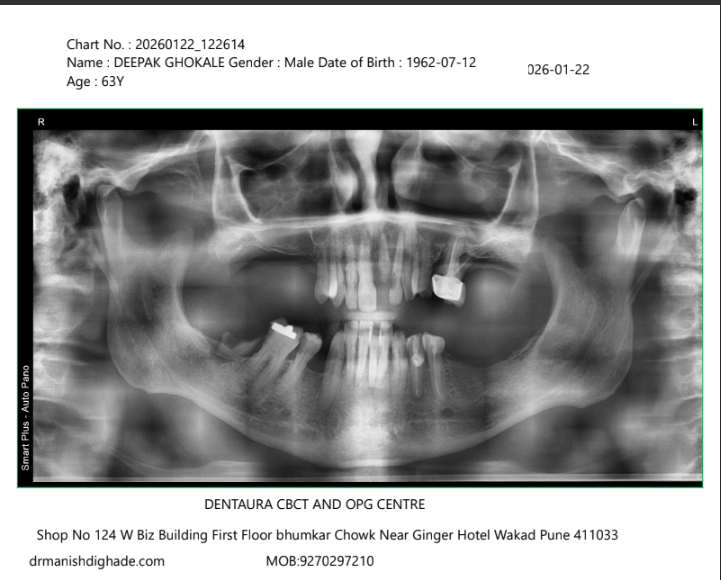

X-Ray Analysis

OPG — Before

OPG — After

Radiographic Findings